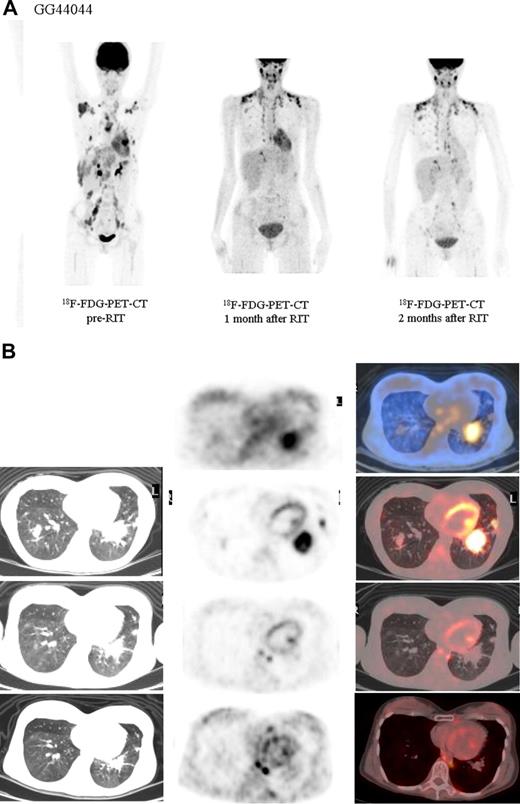

Both HL patients also showed favorable lesion/bone marrow dosimetry estimates after receiving diagnostic 131I-L19SIP, with an absorbed dose of radioactivity to the target lesions—a pulmonary lymphoma lesion (patient HL1) and a left basal pulmonary lesion and a right axillar lymphoma conglomerate (patient HL2)—estimated to be approximately 14 and 22.7 Gy, respectively. The absorbed dose to the red bone marrow was calculated to be 1.3 and 0.85 Gy for HL patients HL1 and HL2, respectively. In HL patient HL1, the SPECT-CT images acquired 12 days after a dose of 5.55 GBq 131I-L19SIP demonstrated selective ED-B FN targeting in multiple parenchymal lung lesions and in enlarged supraclavicular and lumboaortic lymph nodes with all such sites corresponding to high 18F-FDG uptake on baseline PET-CT scans (Figure 6). In the second HL patient (HL2), the SPECT-CT images acquired 12 days after a dose of 3.7 GBq 131I-L19SIP demonstrated selective ED-B FN targeting in multiple enlarged axillar and supraclavicular (both sides), paratracheal, subcarinal, pleural, as well as peritoneal and iliacal (both sides) lymph nodes. ED-B FN–expressing lymphoma lesions were also found in the right and left basal lobes of the lung. All ED-B FN–expressing lymphoma lesions corresponded to high 18F-FDG uptake on baseline PET-CT scans (Figure 7). Both HL patients experienced a partial clinical response according to RESCIST criteria at 1 month after therapy with shrinkage of the sum of diameters of the measurable lymphoma lesions of 44% (134 to 75 mm; baseline to 1 month after treatment) and 39% (417 to 256 mm) for patients HL1 and HL2, respectively. This partial response was confirmed at 2 and 3 months after 131I-L19SIP therapy for both HL patients. The 3 lymphoma patients did not experience any acute toxicity during or after 131I-L19SIP therapy. Mild and transient thrombocytopenia was observed in both HL patients, but not in the SLL NHL patient, with a nadir of 22 and 52 × 109 platelets/L for patients HL1 and HL2, respectively, at 6 weeks after 131I-L19SIP injection.

18F-FDG PET scans and 131I-L19SIP SPECT-CT images from an advanced Hodgkin lymphoma patient (HL1).18F-FDG PET scans show intense glucose metabolism in multiple enlarged mediastinal lymph nodes, intrapulmonary lesions (leftmost column, first 4 images; intrapulmonary lesion marked), as well as in lumboaortic lymph nodes (leftmost image in lowest row). The same patient received intravenous injections of 185 MBq and, subsequently, 5.55 GBq 131I-L19-SIP. SPECT-CT coronal (top right panel) and transaxial images of the thorax (rows 2-4) as well as the upper abdomen (lowest row) are shown, demonstrating selective uptake of 131I-L19SIP into the 18F-FDG–labeled lymphomatous lesions.